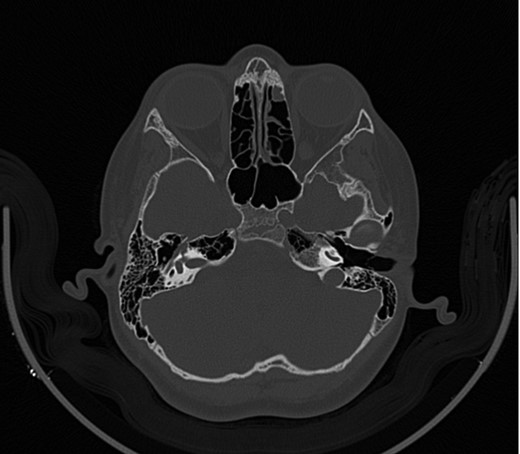

A 14-year-old male patient presented to the ENT clinic with bilateral hearing loss with no other otolaryngological symptoms. History from the patient stated a road traffic accident (RTA) 12 months ago. Meanwhile, the patient had no hearing problems prior to the RTA. Furthermore, detailed history of the accident revealed that the patient had no apparent skull injuries while pure tone audiometry (PTA) on presentation revealed bilateral conductive hearing loss and auditory brainstem response revealed right mild hearing loss and left moderate hearing loss. As a result, he was fitted with hearing aid for four months after presentation and was not compliant to it on the long-term. The patient is a non-smoker and is medically free with normal developmental milestones and negative family history of hearing complaints. Local examination of the ear revealed intact but minimally retracted tympanic membrane bilaterally. PTA was done in 2014 revealed right mild to moderate mixed hearing loss and conductive hearing loss at low frequency (Table 1). Meanwhile, the left ear had mild to moderate sensory hearing loss at high frequency (Table 2). The speech audiogram results show equal canal volume in both ears, less tympanometry pressure on the right ear and less compliance on the right ear (Table 3). The CT showed that both ossicular chains are deranged, and bilateral abnormal ossicles with no fracture or mass (Figures 1–3).

Figure 1:

CT mastoid, deranged right side ossicular disruption.